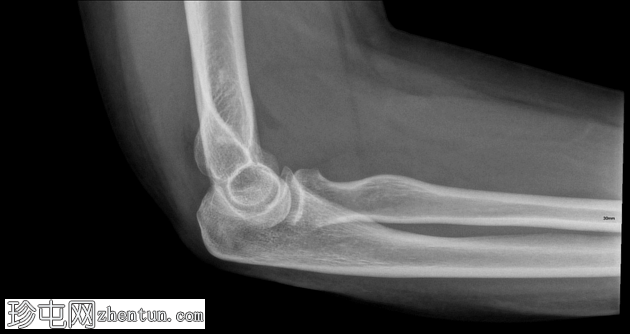

正位

侧位

侧位片显示前后脂肪垫征,提示关节囊扩张。

可见桡骨头轻微凹陷性骨折。

桡骨头骨折通常由肘关节伸直时手掌撑地摔倒所致。侧位X线片上前后脂肪垫征的存在是关节囊扩张(由关节积血和关节积液引起)的重要间接指标,即使皮质骨未见明显损伤,也是隐匿性骨折的标志